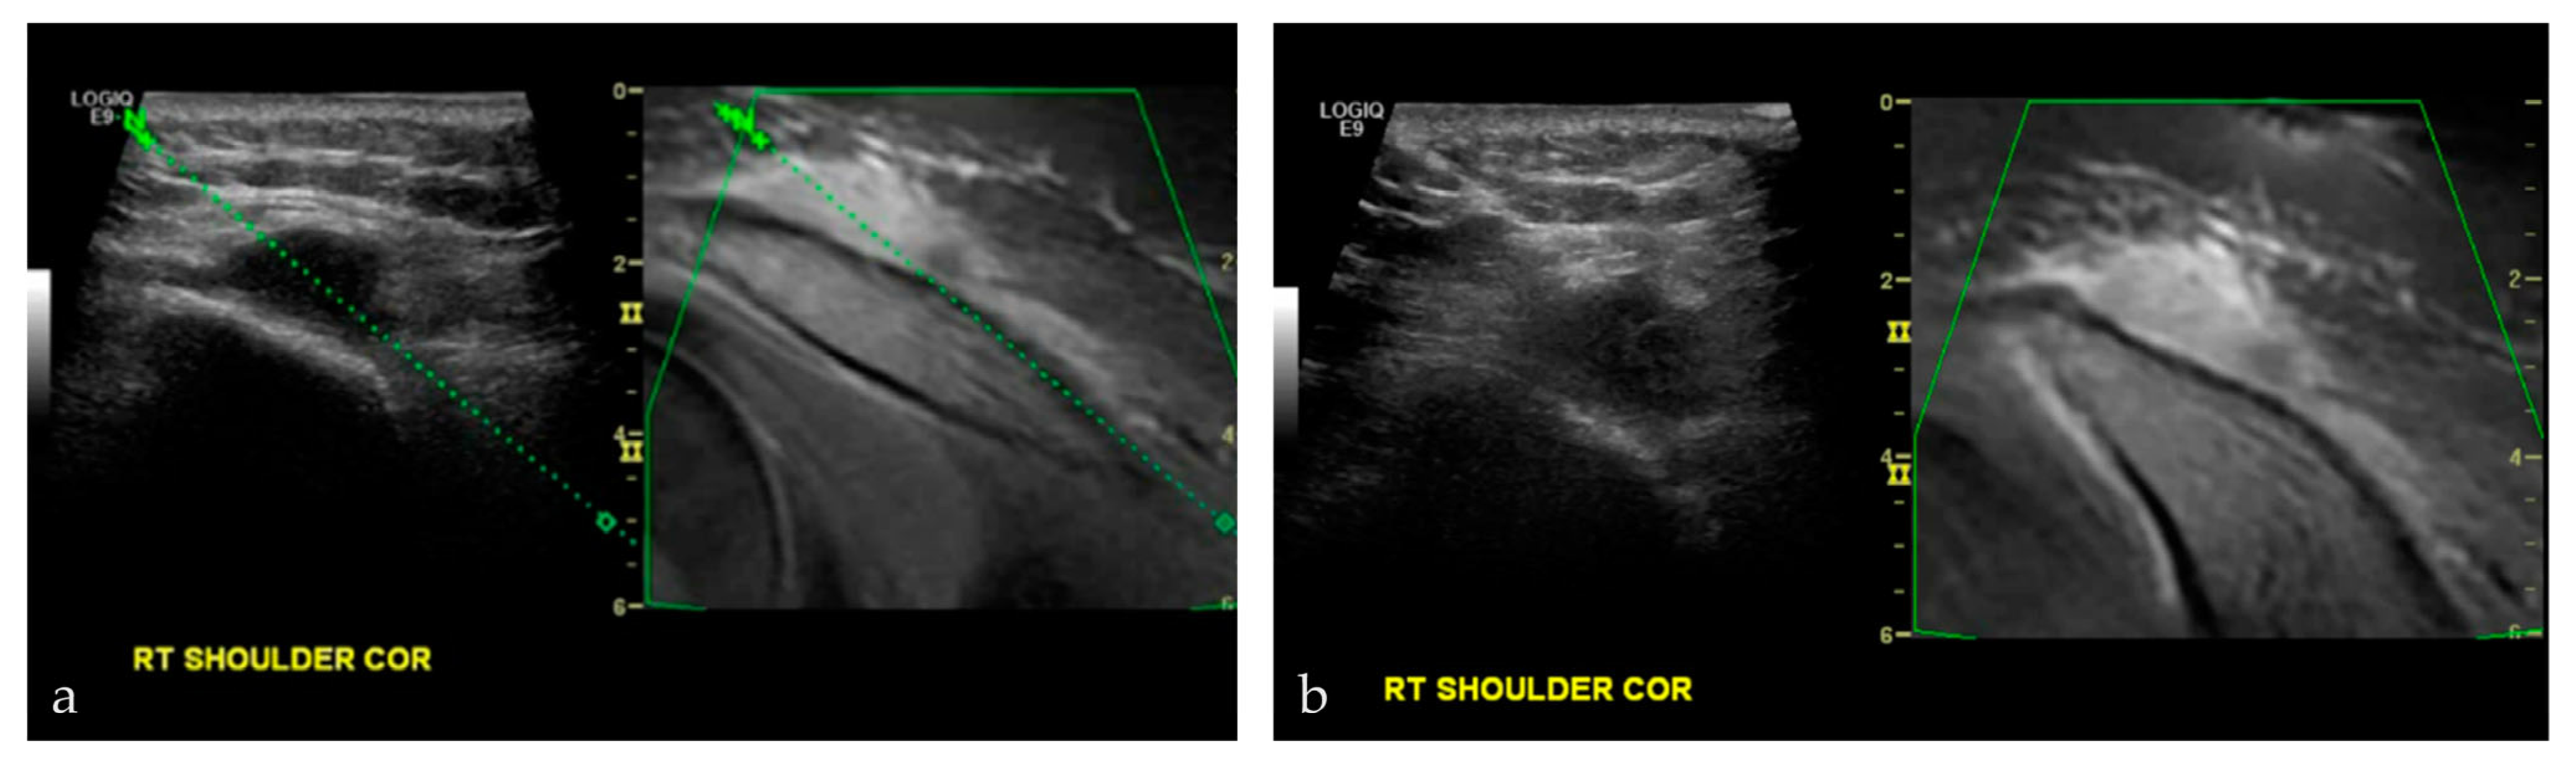

3.2.2. Sports Injuries

- Wong-On, M.; Til-Pérez, L.; Balius, R. Evaluation of MRI-US Fusion Technology in Sports-Related Musculoskeletal Injuries. Adv. Ther. 2015, 32, 580–594. [Google Scholar] [CrossRef]